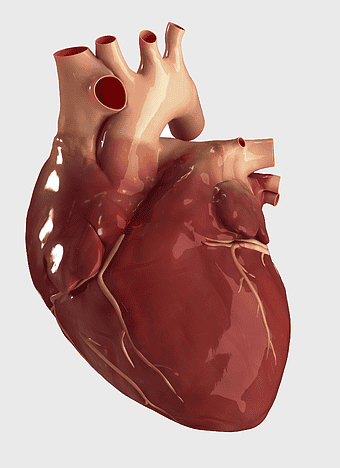

human heart anatomy, cardiac muscle illustration, circulatory system model, heart health visual, cardiovascular organ diagram, medical heart image, visceral structure depiction -

Heart Anatomy Drawing, human heart illustration, human anatomy art, organ depiction, cardiovascular system, medical illustration, anatomical sketch -

human heart anatomy, superior vena cava illustration, systemic circulation diagram, heart rate visual, cardiovascular system study, medical organ depiction, human body organ reference -

human heart anatomy, cardiovascular system illustration, medical heart diagram, heart organ structure, human body organ visuals, anatomical heart drawing, heart health -

human heart diagram, cardiovascular system anatomy, blood vessel chart, free body diagram, circulatory system illustration, medical organ visualization, human anatomy study -